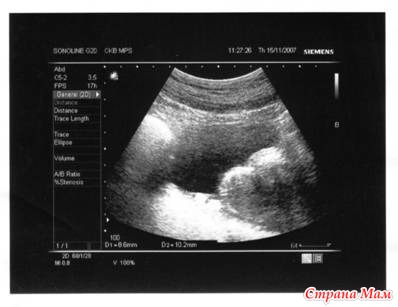

Успокоились, дышим ровнее, это ошибочка. Месячных, кстати, нет. Но такая моральная нагрузка (успокаивала я себя), это просто сбой. Пошла на УЗИ. Тетенька стопитсот раз переспрашивала у меня диагноз по направлению (которое у неё в руках). До сих пор помню её вердикт- хроничекий аднексит, миома матки, множественные серозные узлы. И приписочка внизу- возможна маточная беременность. Я в жизни так не плакала, девочки!